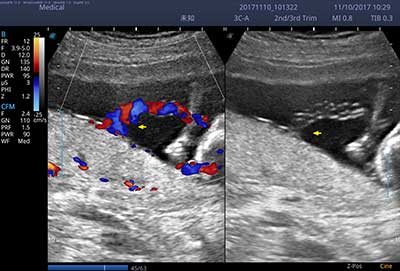

E3便携式彩色多普勒超声诊断系统拥有专业超声技术平台、高度集成化的硬件模块和结构设计、简便的操作流程、支持三探头接口全激活,兼顾了优质图像、轻便机身以及台便两用的临床使用需求。无论在常规超声科门诊检查,还是在急诊、麻醉、ICU、户外等各种应用场景。都能给您带来流程的操作体验。

• SR Flow 高分辨率血流